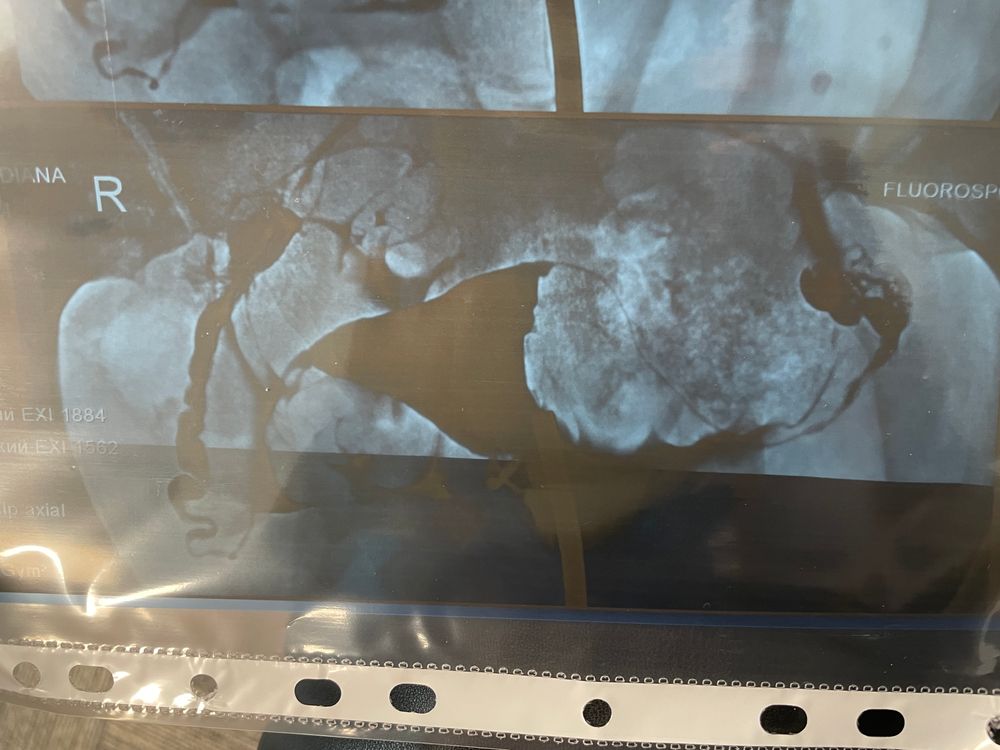

Здравствуйте. Прошла процедуру МСГ. В заключении написали, что обе трубы проходимы, но в левой есть признаки спаечного процесса в ампулярном отделе. Правая труба появилась сразу, а левая на 2ой раз. При этом сказали есть все шансы забеременеть через любую трубу. И контуры полости с левой стороны неровные и нужно исключить патологию эндометрия на гистероскопии. Снимок прилагаю.

Что вы думаете, что нужно сделать? Это хороший результат или не очень? И где именно спайки на снимке?